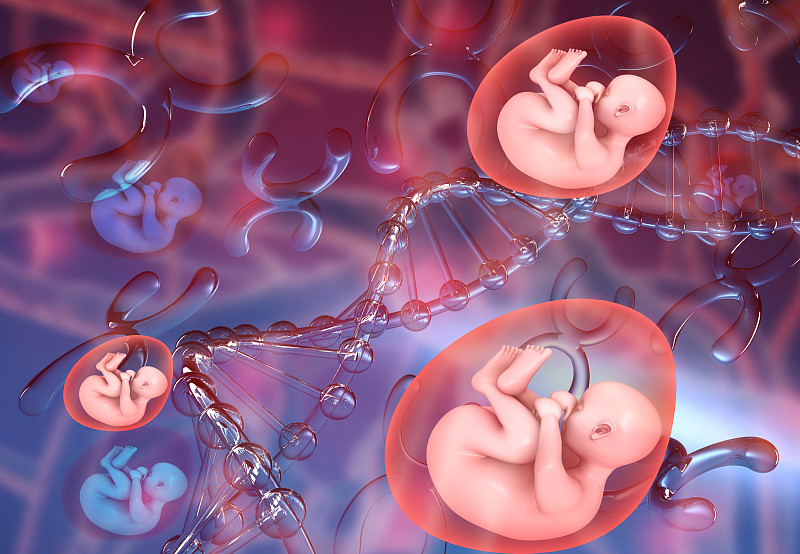

胎儿在子宫里的插图详情